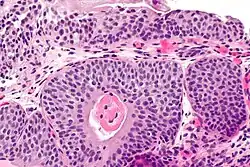

| Micrograph showing cystitis cystica. | |